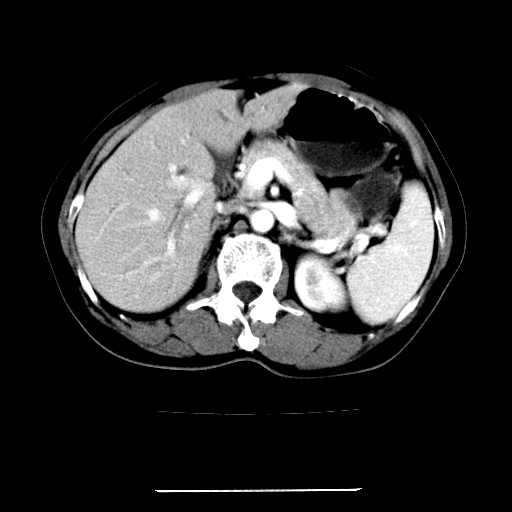

女,67岁,上腹部疼痛一周伴皮肤黄染,无发热。

考虑:肝内胆管结石继发肝内胆管扩张,右肾旋转不良。

肝内外胆管结石并肝内胆管扩张。

肝内外胆管结石并肝内胆管扩张

肝内外胆管扩张,左叶胆管内结石

1、肝门高密度影下层面和胰头层面可见轻度胆管扩张,而静脉和延迟期均未见扫描完胰头,不能完全排除胰头占位。2、肝门部高密度影,考虑钙化或结石。